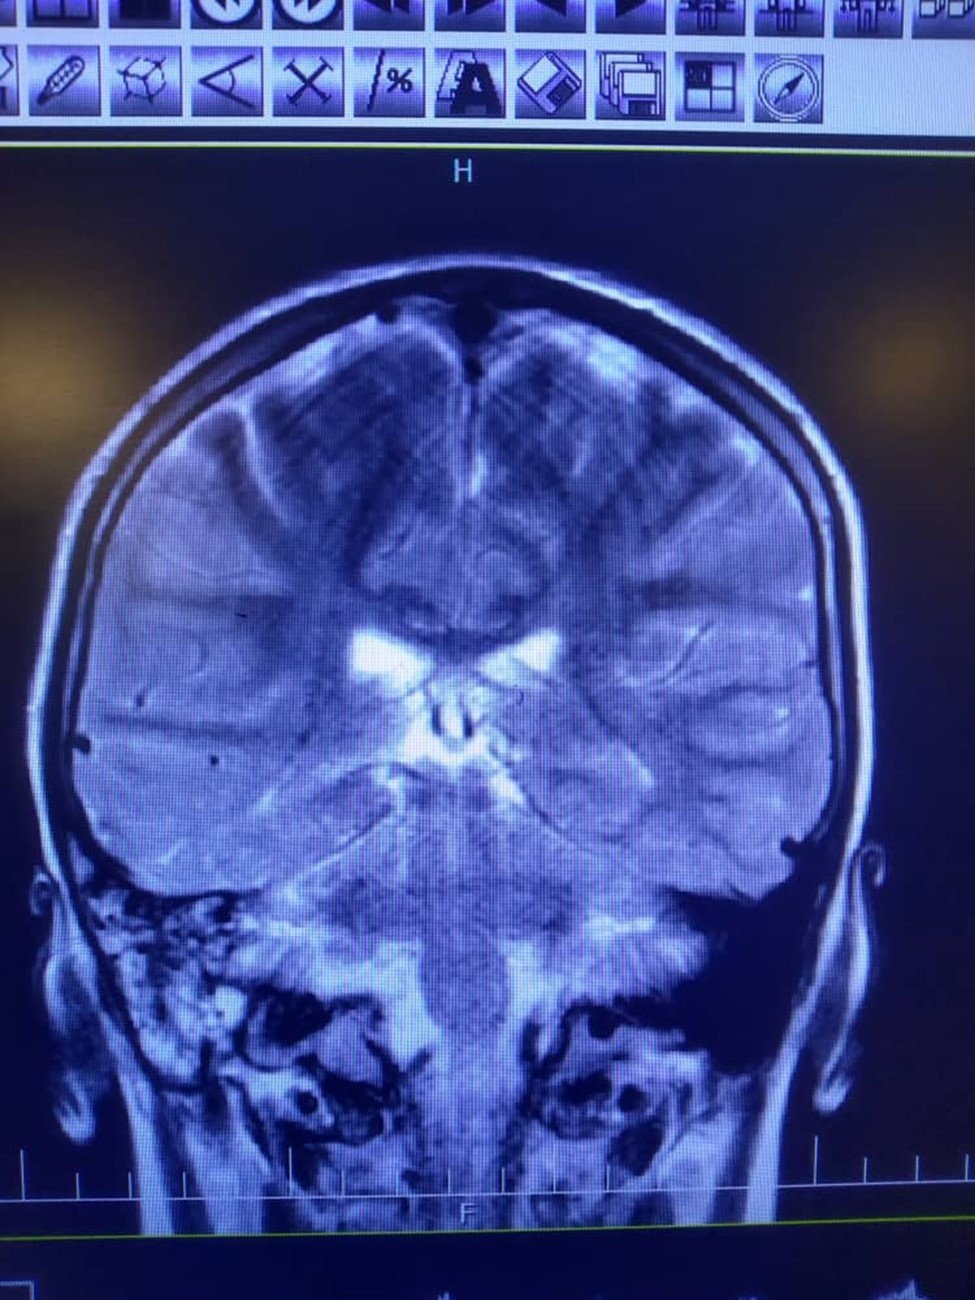

Despite the abnormal manifestation in mastoid cells, the audiometric examination was normal. Due to continuing the headache and right ear, the spiral HRCT of temporal bone without injection was requested. (Figure 2)

Figure 2.High signal intensity in both hemispheres is noted suggestive of meningitis. In T2 sequence there are hyper signal material left maxillary sinuse and bilateral frontal sinuses in favour of sinusitis, polyp and retention cyst in left maxillary sinus is noted. Effusion in right mastoidal air cell is noted.